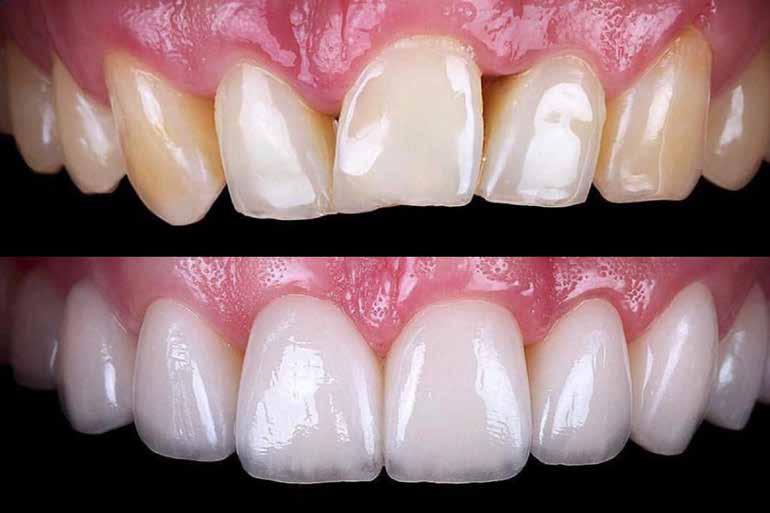

14.00–15.15 Dr. Salem Jusic (Bosznia-Hercegovina): Az anterior fogak különösen esztétikus kompozitrestaurációi

Előadás témái:

- A mosoly architektúrája (az elülső fogak morfológiája)

- Előkészítés (tippek a láthatatlan restaurációkhoz)

- Eszközök és mátrixok

- Hogyan válasszuk ki a megfelelő kompozitot?

- Kompozitrétegezés (mono, duo, polyshade)

- Befejezés és polírozás (tippek és trükkök a magasfényűséghez)